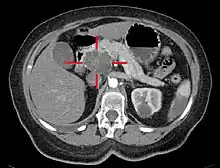

Medical imaging techniques, such as computed tomography (CT scan) and endoscopic ultrasound (EUS) are used both to confirm the diagnosis and to help decide whether the tumor can be surgically removed (its "resectability").[12] On contrast CT scan, pancreatic cancer typically shows a gradually increasing radiocontrast uptake, rather than a fast washout as seen in a normal pancreas or a delayed washout as seen in chronic pancreatitis.[56] Magnetic resonance imaging and positron emission tomography may also be used,[2] and magnetic resonance cholangiopancreatography may be useful in some cases.[32] Abdominal ultrasound is less sensitive and will miss small tumors, but can identify cancers that have spread to the liver and build-up of fluid in the peritoneal cavity (ascites).[12] It may be used for a quick and cheap first examination before other techniques.[57]

.jpg.webp)

A biopsy by fine needle aspiration, often guided by endoscopic ultrasound, may be used where there is uncertainty over the diagnosis, but a histologic diagnosis is not usually required for removal of the tumor by surgery to go ahead.[12]